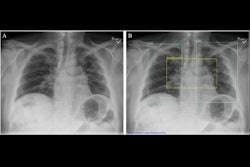

A representative posteroanterior chest x-ray (A) in a 71-year-old male patient who underwent examination due to progression of dyspnea shows bilateral fibrosis (arrows), which was misclassified as airspace disease by all four AI tools. Image courtesy of Radiology.